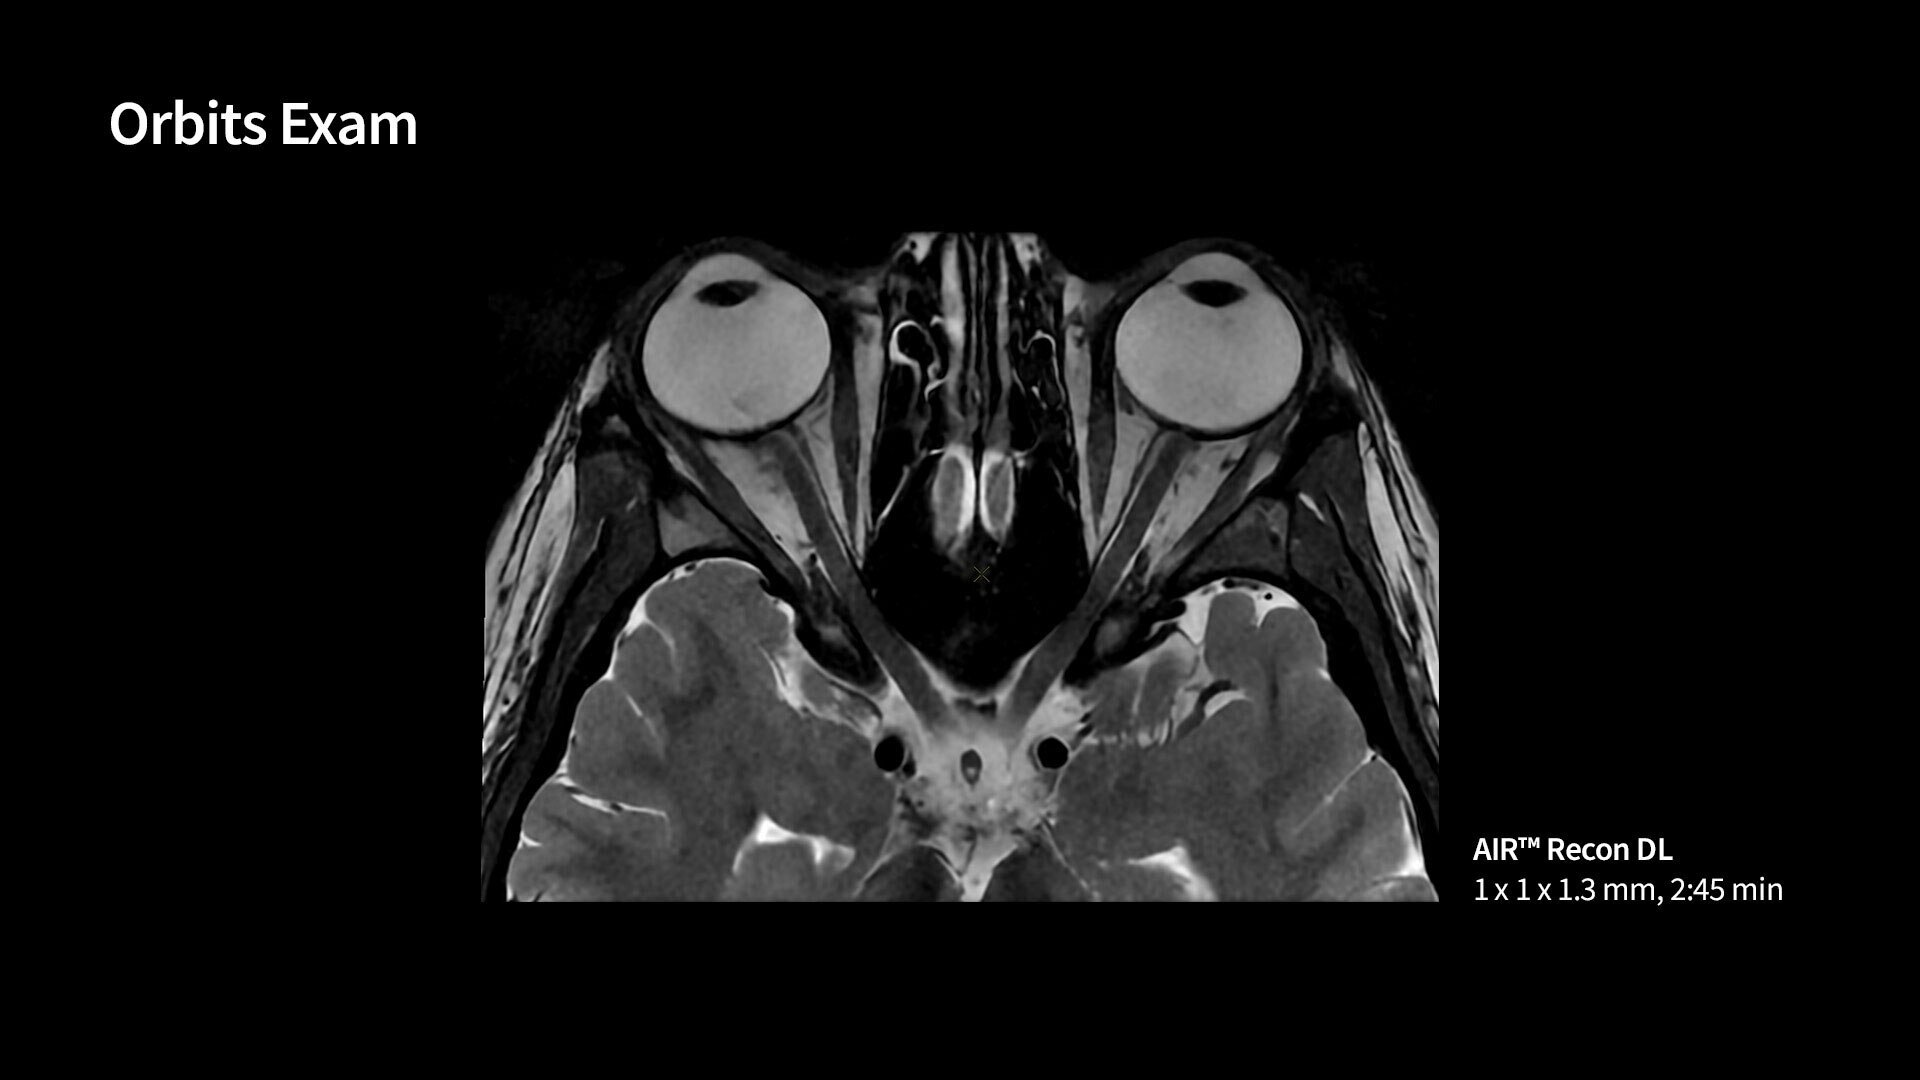

MR image reconstruction with AIR Recon DL

Evolve your MRI scanner's capabilities: experience exceptional image quality without compromising scan time.